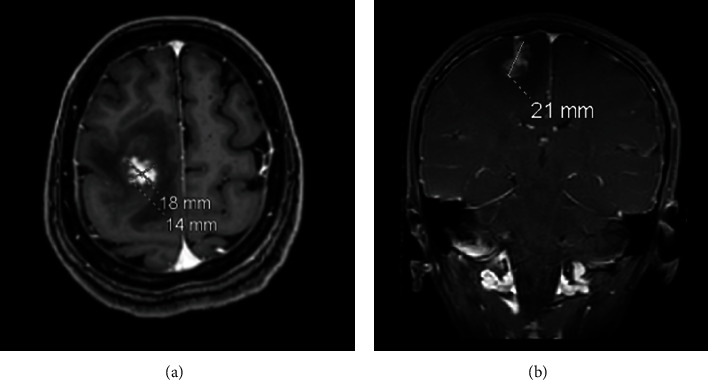

Introduction: Schistosomiasis is a parasitic infection caused by schistosome invasion of blood circulation. Neuroschistosomiasis is a severe cerebral complication that accounts for less than 2.3% of reported cases. Patients present with progressive encephalitis, seizures, or both. Management includes antiparasitic medications, steroids, and surgical intervention. Case Presentation. We report a case of a 44-year-old female who presented to the ER with a history of transient loss of consciousness (LOC) and seizure. Radiological investigations revealed a right frontal brain lesion. Histopathological results confirmed the diagnosis of schistosomiasis.